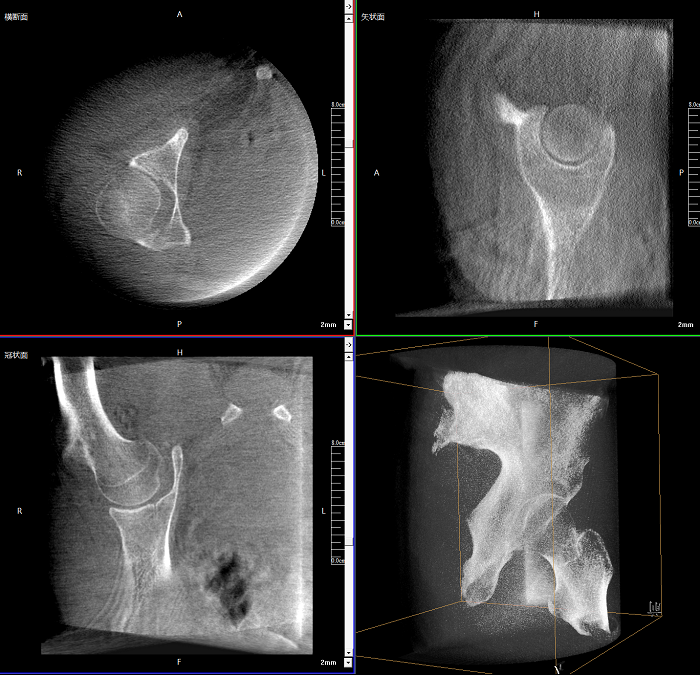

該設(shè)備可進(jìn)行快速的術(shù)中三維掃描,生成類CT斷層圖像和立體3D圖像,保障植入物置入效果。廣泛適用于骨科、脊柱外科、矯形外科、創(chuàng)傷骨科等其他領(lǐng)域。

●極速成像僅需8秒,從數(shù)據(jù)采集結(jié)束到完成三維重建斷層影像